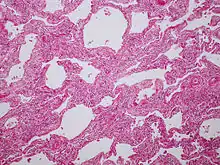

La Cannabiosis se ha relacionado con una respuesta alérgica de naturaleza respiratoria denominada neumonitis por hipersensibilidad (NH). Se trata de una reacción inflamatoria pulmonar tras exposición a una sustancia antigénica, provocando una afectación difusa de los espacios alveolo-intersticiales y bronquiolos terminales. Su mecanismo de acción se basa en el daño que provoca el polvo tras instalarse en las paredes bronquiales, liberándose histamina y serotonina.[2]

El curso clínico puede manifestarse de forma aguda, subaguda, en función de la intensidad de exposición. Las exposiciones mantenidas dan lugar a la forma crónica con evolución a la fibrosis pulmonar. La función pulmonar disminuye tras unas horas de exposición en el trabajo y mejor tras finalizar la jornada laboral. Es una enfermedad progresiva en la que si hay una exposición continuada durante muchos años, puede incluso provocar la muerte por fracaso en el ventrículo derecho.[3]

Exposición continua en el tiempo pero de baja intensidad. Evoluciona hacia insuficiencia respiratoria crónica hipoxémica, fibrosis pulmonar, hipertensión pulmonar, dificultad para la realización de cualquier esfuerzo y cor pulmonar.